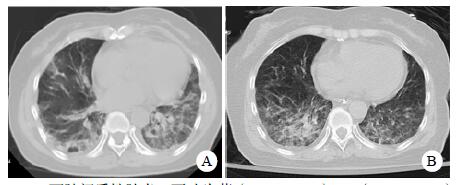

| A:两肺间质性肺炎,下叶为著(2019-06-23);B:(2019-09-30)两肺间质性肺炎,下叶为著,较前(2019-06-23)部分好转 图 3 患者胸部HRCT结果 |

转入ICU后呼吸机辅助通气、甘露醇100 mL/8 h静滴脱水、头孢呋辛1.5 g/12 h静滴抗感染,肠内营养等支持治疗。当晚血常规:白细胞13.3×109/L,中性粒细胞百分比85.3%,C反应蛋白17.1 mg/L,降钙素原0.64 ng/mL。脑室外引流术后次日血化验:白细胞16.6×109/L,中性粒细胞百分比92.8%,C反应蛋白78.4 mg/L;从脑室外引流管留取脑脊液检验:有核细胞6×106/L,红细胞1 960×106/L,蛋白含量1.717 g/L,葡萄糖4.72 mmol/L,细菌培养阴性,涂片未找到细菌;复查头颅CT示:脑室扩张好转,右侧丘脑、左侧岛叶病变伴出血(图 2);胸部CT示,两肺间质性肺炎下叶为著,较前(2019年6月21日)部分好转(图 3)。考虑到炎症指标升高,遂改哌拉西林他唑巴坦3.375 g/12 h静滴抗感染。此后经脑室外引流管反复留取脑脊液送检涂片及培养均阴性。术后第5天行“导航下立体定向颅内病灶活检术+双侧omaya囊置入术”,术中穿刺液呈黄色黏稠脓性,考虑脑脓肿,留取脓液送高通量测序(next-generation sequencing, NGS),并升级为美罗培南2 g/8 h联合利奈唑胺0.6 g/12 h静滴抗感染治疗。术后第7天患者突发血压升高、瞳孔不等大,昏迷程度加深;急查头颅CT示,双侧脑室钻孔引流术后改变,双侧侧脑室引流管走形区出血伴血肿形成;右侧丘脑区积液、积血,双侧脑室积血新发(图 4),甘露醇加量至250 mL/8 h联合地塞米松5 mg/6 h静滴加强脱水;当日术中脓液高通量测序结果回报:皮疽诺卡菌(序列数52 867个)、支气管戈登菌(序列数10个)。确诊脑诺卡菌病,抗菌治疗方案改为亚胺培南西司他丁0.5 g/6 h静滴,联合利奈唑胺0.6 g/12 h和复方磺胺甲恶唑片(0.48 g/片)3片/6 h口服。此后患者仍伴低热,炎症指标呈上升趋势。术后2周患者再次突发血压升高、瞳孔不等大、对光反射消失、神志深昏迷,急查头颅CT示再发脑疝(图 5),急诊行“去骨瓣减压术+脑内血肿清除术”,术后患者仍呈深昏迷状态,双侧瞳孔散大、对光反射消失,次日自动出院。